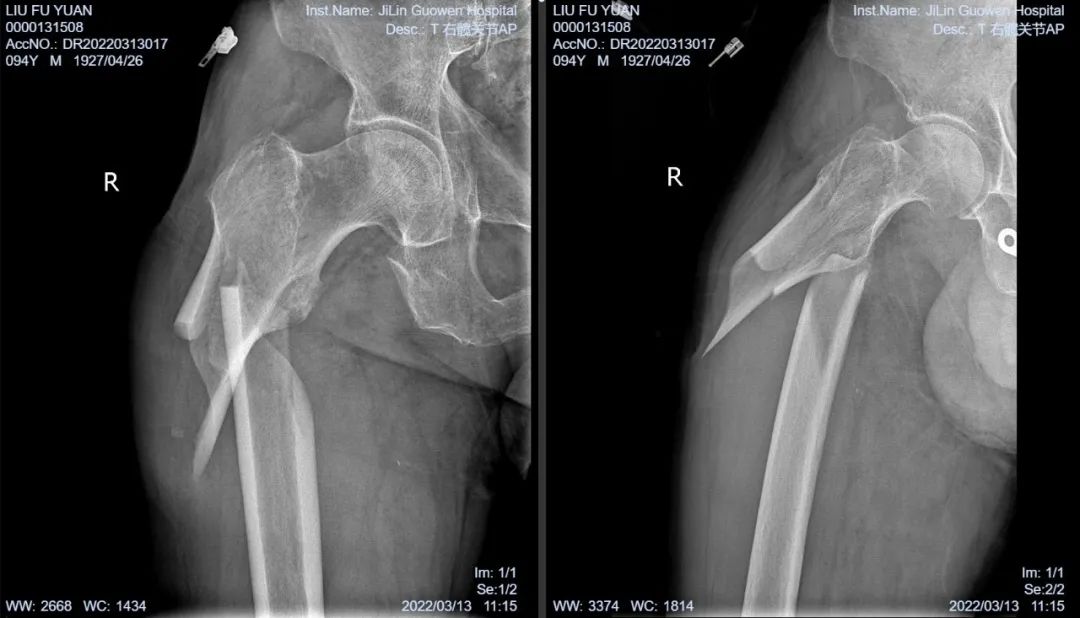

3月13日伴著急促的腳步聲、轆轆的車輪聲,夾雜著患者痛苦的呻吟聲,一位94歲的高齡老人被急診科醫(yī)護(hù)人員緊急送至骨科療區(qū)。這是怎么回事?呂國(guó)褔主任帶著值班醫(yī)生在做好防護(hù)措施后,第一時(shí)間來(lái)到患者病床前,經(jīng)急診科醫(yī)生診斷告知為 “股骨近端粉碎性骨折”,患者右大腿近端嚴(yán)重畸形,骨折端已經(jīng)刺穿前方肌肉直達(dá)皮下,局部皮膚高高隆起,局部皮膚有挫傷灶,呈青紫色,皮膚變薄,皮膚外可明顯觸及骨折斷端,右股骨X線片示:右股骨近端粉碎性骨折,斷端移位明顯,斷端銳利,近斷端位于前方皮膚下,局部皮膚隆起?;颊咛弁磩×?,痛苦難耐,測(cè)生命體征:血壓:220/110mmHg。